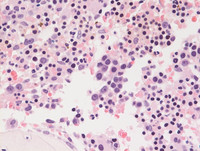

Aspirate smears of marrow

Bone marrow aspirate smear demonstrating dysplastic megakaryocytes on the left with 2 separate nuclear lobes while on the right side of the field to large immature pronormoblasts (erythroid precursors) are noted.  The image on the right and the bottom left show dysplastic megakaryocytes and megaloblastoid erythroid precursors. A large eosinophilic myelocyte is also seen in the center of the field on the image in the bottom left.